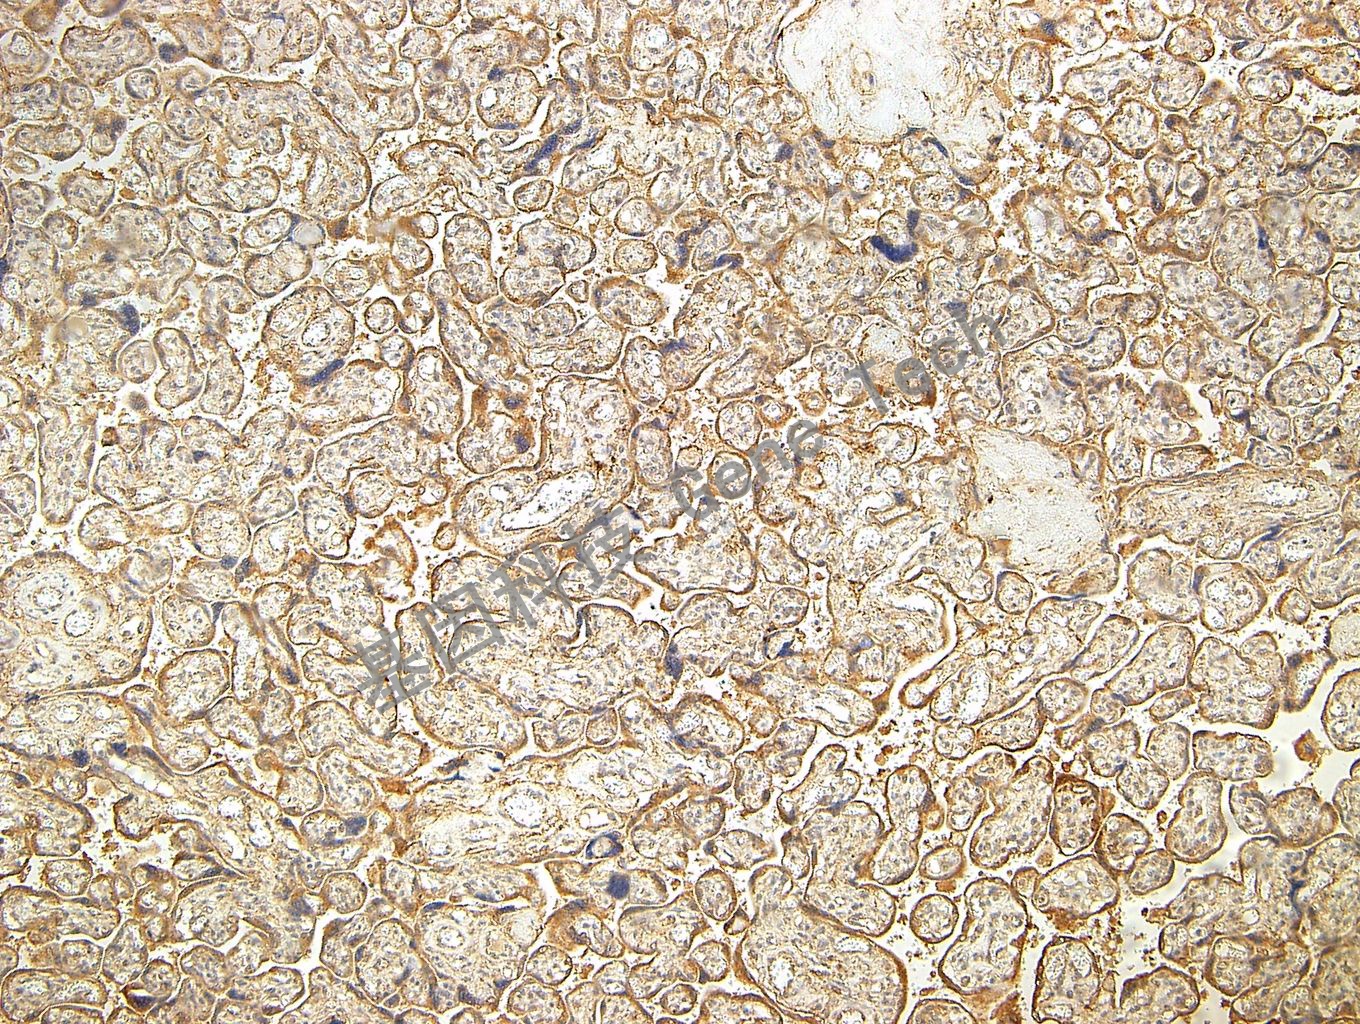

胎盘石蜡切片,用 PI3K P85(GT2214)染色,细胞浆阳性,DAB 显色。